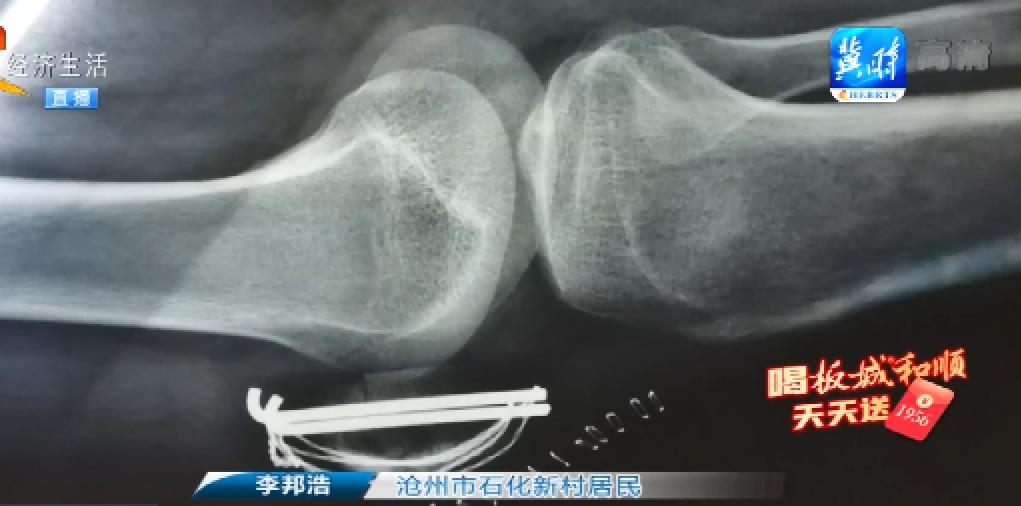

河北省滄州市石化新村小區(qū)的兩位住戶給我們打來電話說,他們小區(qū)以前屬于煉油廠宿舍,后來小區(qū)進(jìn)行了三供一業(yè)的改造,自來水也移交到了市政,這本來是件好事,但讓他們?nèi)f萬沒有想到的是,伴隨著小區(qū)改造的進(jìn)行,發(fā)生了兩起意外,而這意外就發(fā)生在他倆的身上,到底是怎么回事呢? 頭幾個(gè)月吃點(diǎn)東西光吐。第一個(gè)月連衣服都不能脫,手怎么放怎么疼,疼的天天吃止疼藥。 1 鄭智英的遭遇還要從小區(qū)改造開始說起,石化新村小區(qū)從2019年開始進(jìn)行三供一業(yè)改造,小區(qū)更換了新的自來水管道,可是剛剛更換一年時(shí)間,意外發(fā)生了。 自來水管爆了? 1 噴水結(jié)冰的位置正好位于單元樓前,在2020年12月30日兩位居民接連摔倒。 我尋思把冰邁過去,我這一邁不小心。 直接把膝蓋跪碎了,粉碎性骨折。 1 鄭智英和李邦浩兩位居民相繼就醫(yī)治療,鄭智英被診斷為左手骨折而李邦浩則為左側(cè)膝蓋粉碎性骨折,分別花費(fèi)了7000多元和兩萬多元,然而,隨后的維權(quán)道路并不順暢。 溝通過,當(dāng)時(shí)這位大姨帶著我去找自來水公司,他們說給解決,就是一直推,到現(xiàn)在也沒有一個(gè)說法,說是給解決到現(xiàn)在都過去五個(gè)月了。 1 事情到現(xiàn)在為何一直沒有得到明確回復(fù)呢?隨后記者和兩位當(dāng)事人一起找到了負(fù)責(zé)解決此事的滄州市供水排水集團(tuán)有限公司建設(shè)南路營業(yè)所。 1 在電話溝通后,供水公司的另外一名工作人員趕了過來。 走法律程序,才能批花了多少錢,然后我們報(bào)到集團(tuán)去走審批。 走法律程序? 對。 你們是收費(fèi)處,客服部,這個(gè)自來水管不是你們建的,我知道,是不是你們自來水總公司建設(shè)的? 是自來水總公司建的,沒錯(cuò)。 這事還是你們自來水公司來負(fù)責(zé)? 是,這個(gè)賠償需要集團(tuán)那邊來審批,所以我們這邊必須得走這個(gè)程序。 也就是說不走法律程序,你們這筆錢沒辦法往下批? 對,而且還得要花了多少錢那個(gè)票據(jù)。 事情過去五個(gè)月了,今天在我們的記者面前,滄州市供水排水集團(tuán)有限公司總算是表明要承擔(dān)這個(gè)責(zé)任。那既然早知情,為何要一推再推,如果不是記者的到來,那兩位居民的賠償又要拖到什么時(shí)候?在這兒我們也希望,自來水公司能夠積極的來解決這個(gè)問題,配合居民辦理相關(guān)賠償工作,不要再讓居民涼透了心。 戳下面視頻 看詳細(xì)內(nèi)容